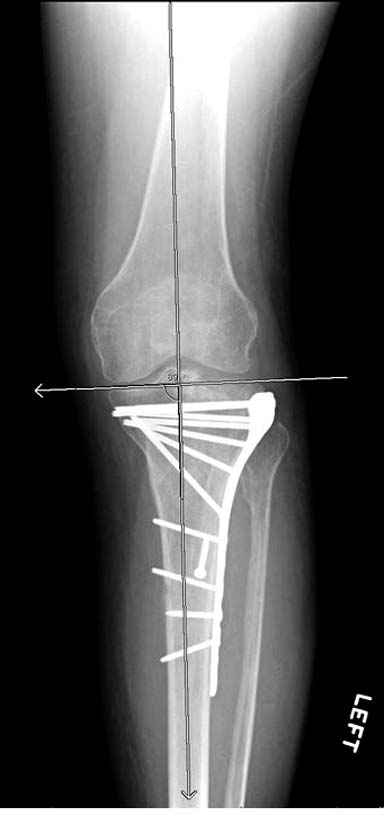

Если там действительная импрессия, пустое место без структуральных заполнителей, кость или синтетические материалы, не восстановится, а образуется коллапс, и ось конечности поведет после нагрузки. Кроме того там возможно "болт стяжка"?, в медиальной стороне выступает за кортекс, можно было укоротить! Потом создается впечатление, что не соответствуют мыщелки большеберцовой и бедренной костей? Покажите снимок.

Здесь пару случаев для сравнения,...в первых 1-4 слайдах метод фиксации одним фиксатором, как видно после 8 месяцев сохранилась ось. С 5 по 9 вариант двумя пластинами...